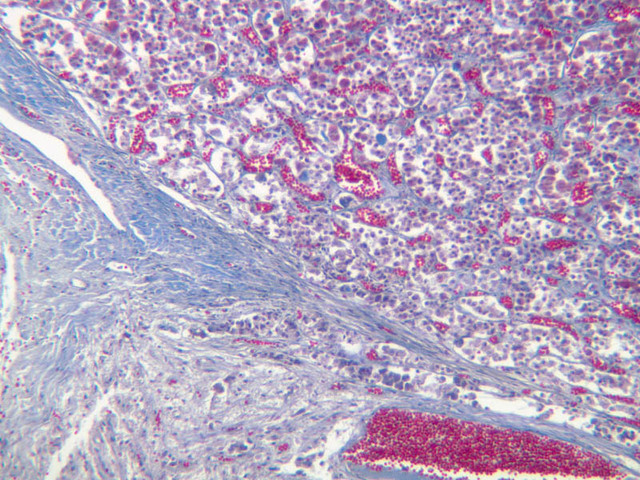

The adenohypophysis arises from oral ectoderm and forms the largest subdivision of the pituitary gland. It consists of three regions: (1) pars tuberalis, which wraps around the pituitary stalk; (2) pars distalis, which makes up most of the anterior portion of the adenohypophysis; (3) pars intermedia, which lies between the pars distalis and the pars nervosa of the neurohypophysis and is characterized by the presence of colloid-filled cysts. In H&E-stained sections, the adenohypophysis is darker than the neurohypophysis (B-63, H&E [2.5x, 10x-labeled, 20x]; B-64, aldehyde fuchsin [2.5x, 10x, 20x, 40x]; B-65, trichrome [2.5x]).

The neurohypophysis arises as an outpocketing of neuroectoderm from the floor of a portion of the brain called diencephalon. It is divisible into the pars nervosa, which forms the posterior portion of the main mass of the pituitary, and the infundibulum, or pituitary stalk. In H&E-stained sections, the neurohypophysis is distinctly eosinophilic. The adenohypophysis (anterior pituitary) has three different types of secretory cells, which are best visualized in the trichrome-stained preparation on slide B-65: (1) acidophils have a reddish staining cytoplasm, owing to the presence of secretory granules. These cells secrete growth hormone (GH) and prolactin (PRL); (2) basophils are slightly larger cells with bluish staining granules present in the cytoplasm. These cells tend to occur in small groups or clusters. Basophils are responsible for the production of thyroid stimulating hormone (TSH), adrenocorticotrophic hormone (ACTH), and the gonadotrophic hormones follicle stimulating hormone (FSH) and luteinizing hormone (LH ); (3) chromophobes or C cells are smaller cells and have only a small amount of poorly staining cytoplasm (B-63, H&E [2.5x-labeled, 10x, 20x, 40x-labeled] [2.5x, 10x, 20x, 40x-labeled]; B-65, trichrome [2.5x, 10x, 20x, 40x-labeled] [2.5x, 10x, 20x, 40x] [10x, 20x, 40x-labeled] [2.5x, 10x, 20x, 40x] [2.5x, 10x, 20x, 40x]). What is the target organ of each of the hormones produced by the adenohypophysis? Note the rich vascularity of the adenohypophysis. Can you describe the blood supply and its significance?

The adrenal gland (slide B-59, H&E [2.5x-labeled, 10x-labeled, 20x, 40x-labeled] [2.5x, 10x-labeled, 20x, 40x]; B-60, H&E [2.5x-labeled, 10x, 20x, 40x]; B-62, H&E [10x, 20x, 40x] [2.5x, 10x]) is a composite organ consisting of two functionally, structurally and embryologically different parts—an outer cortex and an inner medulla. Observe the gland at low power. Find the loosely organized tissue that comprises the medulla and the partially-separated columns of cells that make up the cortex. Scan the capsule and the tissue around it, looking for nerves and blood vessels. Study the pattern of cortical vasculature. In a pattern similar to that seen in the pars distalis of the pituitary, sinusoids run along the edges of columns or cords of cells. Owing to different arrangements of its constituent cells, the adrenal cortex has a layered appearance. From the capsule inward, these cortical layers are known as the zona glomerulosa, the zona fasciculata, and the zona reticularis.